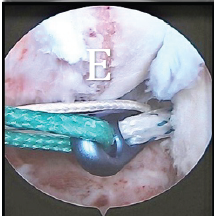

Arthroscopic Fixation of Acute Reverse Bony Bankart Lesion using Cancellous Cannulated Screws: A Rare Case Report

Rahul Kakran , Ashish Kumar Agarwal , Vinay Sharma , Vipin Tyagi , Kamappa Rajappa Binduvaraprasad

………………………………p.255-261